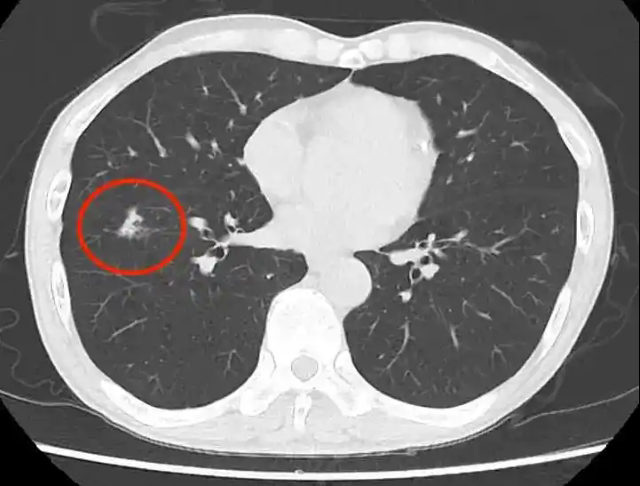

肺结节:肺结节是胸部CT检查中经常发现的一种病变。它表现为肺部的圆形或类圆形结节影,直径一般小于3cm。肺结节的性质多种多样,可以是良性的,如炎性结节、结核球等,也可以是恶性的,如肺癌。对于肺结节的诊断要点,首先要观察结节的大小、形态、边缘特征、内部密度等。较小的结节(小于5mm),如果边缘光滑、密度均匀,多为良性结节,建议定期随访观察。而对于较大的结节(大于8mm),尤其是边缘有毛刺、分叶,内部密度不均匀,或者存在胸膜牵拉征等恶性征象的结节,需要进一步进行增强扫描、PET - CT检查或经皮肺穿刺活检等,以明确其性质。